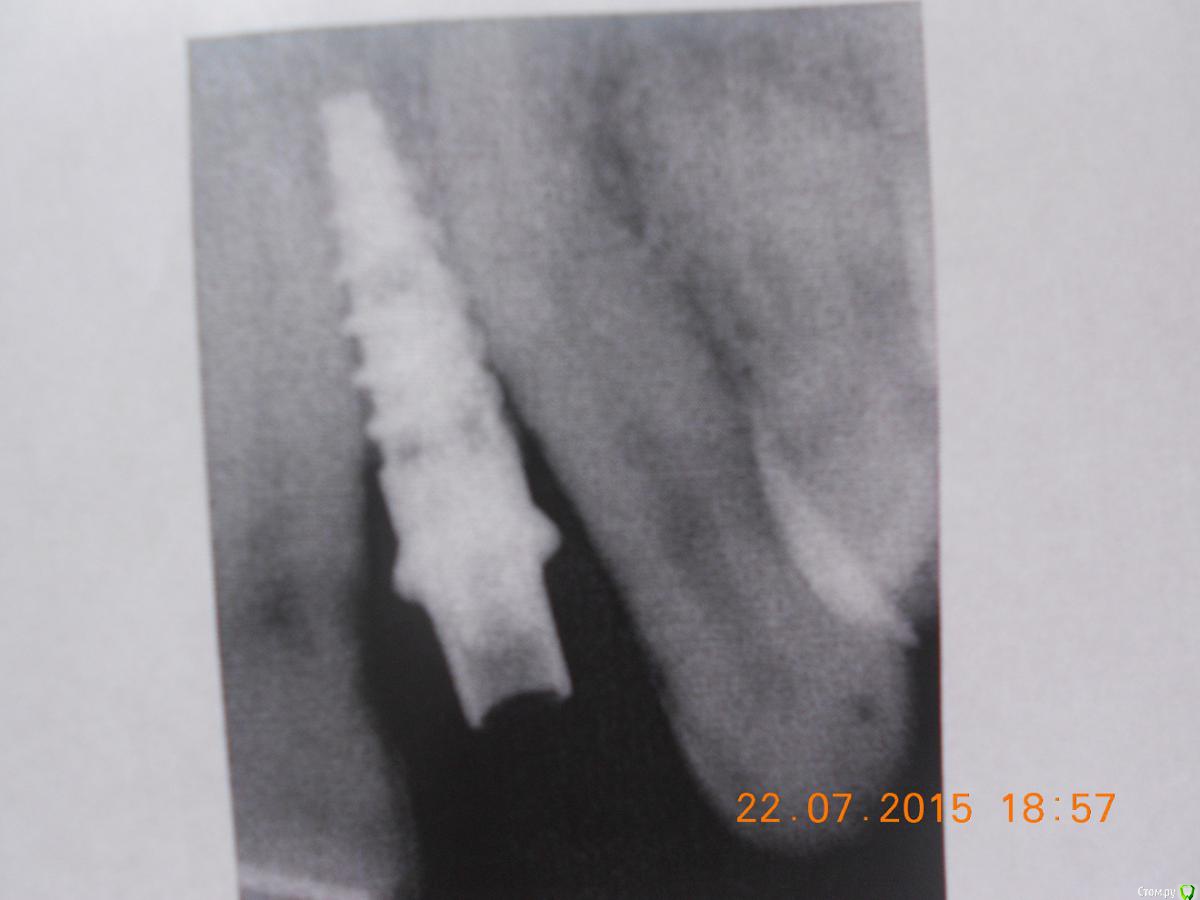

holodova.viktori Опубликовано 22 июля, 2015 Поделиться Опубликовано 22 июля, 2015 Добрый день, прошу помочь принять решение,что делать с имплатном.Поставили на ВЧ два импланта в октябре. Операция вроде бы прошла успешно, ничего не беспокоило. Через 4 мес. установили формирователь десны, проде бы тож все нормально было (снимки прилагаю).Еще через 2 недели отправили к ортопеду. И вот тут когда стал он выкручивать формирователь- стало больно очень-очень внутри кости , итог-имплант выкрутили. На второй имплант установили временную коронку и я с ней отходила ок. 3мес.,вокруг десны возникло локальное воспаление-отправили к пародонтологу,он к хирургу опять,хирург ничего критичного в импланте не увидел.Воспаление прошло-метрогилом мазала,календулой полоскала. И вот когда ортопед стал выкручивать временную коронку-стало опять больно,боль внутри кости опять.Послали на снимки. Хирург посмотрел снимки, потрогал зуб(временный кот), грит наблюдается убыль кости и подвижность имплатна 1 ст. И сейчас предлагает либо не трогать ничего и ходить с временной коронкой столько-сколько прохожу (грит от 2 мес. до неск.лет, те вопрос выпадения импланта-эт вопрос времени просто), либо удалять имплант.Консультировалась с несколькими др. хирургами они грят-необх.откручивать временную коронку и смотреть что с имплантом-выдерживает ли он нагрузку или подвижен, ели подвижен-удалять однозначно, ждать 6-9 мес. пока восстановится объем костной ткани и потом решать что делать дальше.И пока ходить со съемными протезами.И все они грят,что изначально места было недостаточно,для имплантов и есть ошибки хирурга на стадии планирования операции и выбора р-ра имплантов.Очень прошу прокомментировать ситуацию. Ссылка на комментарий

krokomot Опубликовано 22 июля, 2015 Поделиться Опубликовано 22 июля, 2015 Я так понимаю боковые резцы у вас всю жизнь отсутствовали.По мне имплант слишком близко расположен к корням соседних зубов. Прогноз у него весьма сомнительный. 1 Ссылка на комментарий

chervoncevdaniil Опубликовано 22 июля, 2015 Поделиться Опубликовано 22 июля, 2015 А почему есть риск потерять соседние зубы? Я просто тож склоняюсь к удалить,восстановиться и потом решить,что делать.Для установки имланта должны быть определенные условия,в частности расстояние до соседних зубов МИНИМУМ 1.5 мм,если этих 1.5 мм нет,то либо это расстояние нужно создать(как вариант ортодонтия),либо имплантация не проводится.Никакой подвижности быть не должно,там сейчас воспалительный процесс,который ведет к убыли кости,мой совет вам имплант убирать,чуда не произойдет и подвижный имплантат не станет устойчивым,нужно начинать лечение заново,как бы это не печально звучало 3 Ссылка на комментарий